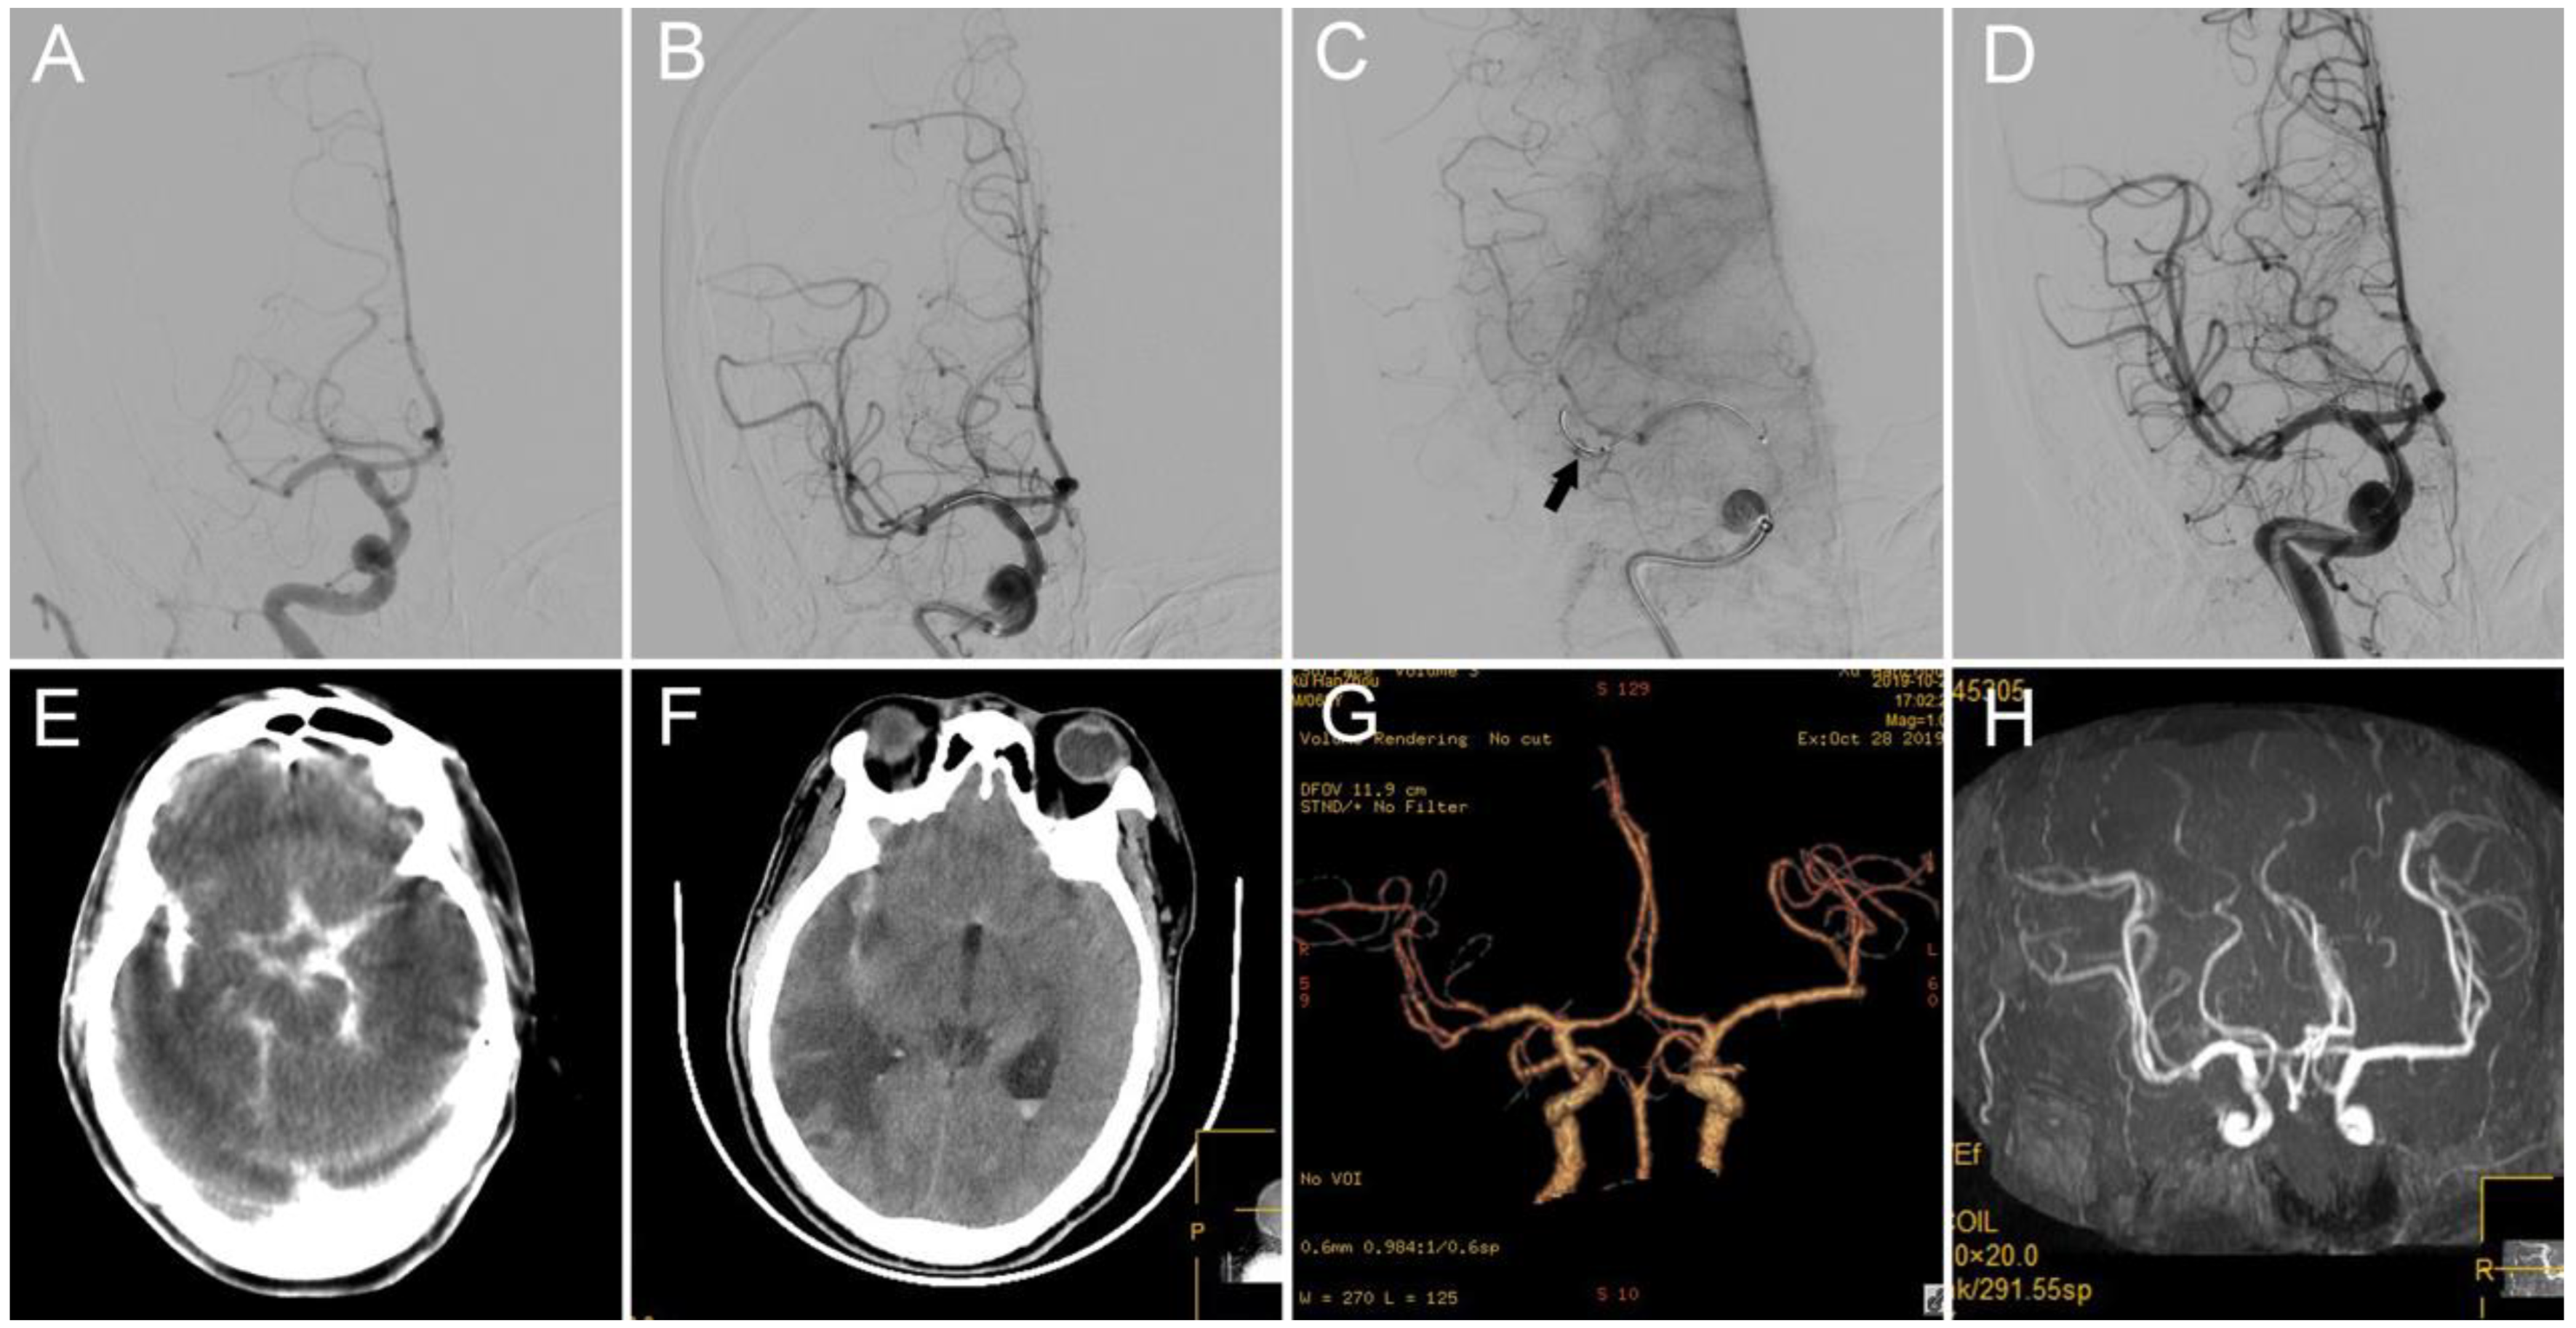

3. Cases 1 and 2: Middle Cerebral Artery (MCA) M1 Occlusion

4. Case 3: Internal Carotid Artery (ICA) Terminus Occlusion

| 1 | R-M1P ICAS | IV heparin | No | Stent retriever + Balloon angioplasty | 1 | RM1D | Perforation with microwire/microcatheter when traversing lesion site | IA thrombin | No new hemorrhage | mTICI 3, mRS 4 at 3 months |

| 2 | L-A3 ICAS | IV heparin | No | NA | NA | L-A2 | Perforation with microwire/microcatheter when traversing clot | IA thrombin | No new hemorrhage | mTICI 0; death at 3rd days after operation |

| 3 | L-ICA terminus ICAS | IV heparin | No | Balloon angioplasty | NA | L-ICA terminus | Perforation with microwire/microcatheter when traversing lesion site | IA thrombin | No new hemorrhage | mTICI 3, mRS 3 at discharge |

| 4 | R-M1D ICAS | IV heparin | No | Stent retriever | Solitaire 4 × 20 1 pass | R M1D | Resistance withdrawing stent retriever | IA thrombin | No new hemorrhage | mTICI 2b, mRS 3 at 3 months |